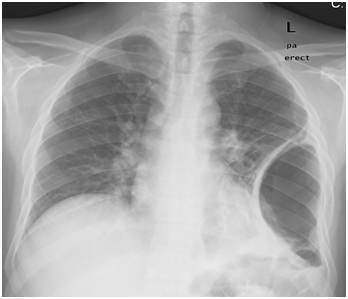

After five days patient returned with the complaints of persistent headache, nasal obstruction, rhinorrhea, right-sided otorrhea and dry cough. He was sick and but still afebrile. He was admitted and right ear swab was sent for culture and sensitivity. The nasal and ear swabs yielded no growth. He was put on IV antibiotics with nasal and antral irrigations twice-daily. His baseline blood works including CBC and renal functions were normal but ESR was 88mm. c-ANCA was sent as Wegener’s granulomatosis was also one of our differential diagnoses. Chest x-ray was within normal except for a left hilar shadow (Figure 1). Biopsy taken under local anesthesia from the edges of septal perforation was reported as non-specific inflammation.

Figure 1 Left hilar opacity.